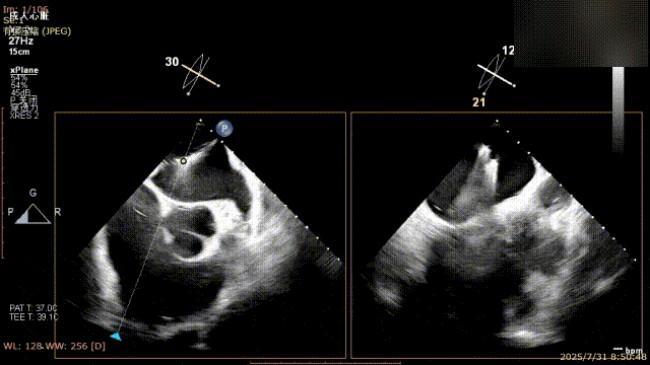

解离前三维

解离后瓣叶及反流

解离后三维

平均跨瓣压差